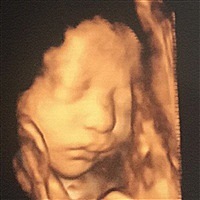

孕35周+1天

我怀孕前一个月做了胆结石手术全麻的 ,还做了两次磁共振呢!现在小孩也挺好的。产检都一次过!可能跟人的体质有关系吧。